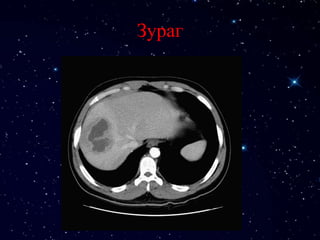

Зураг